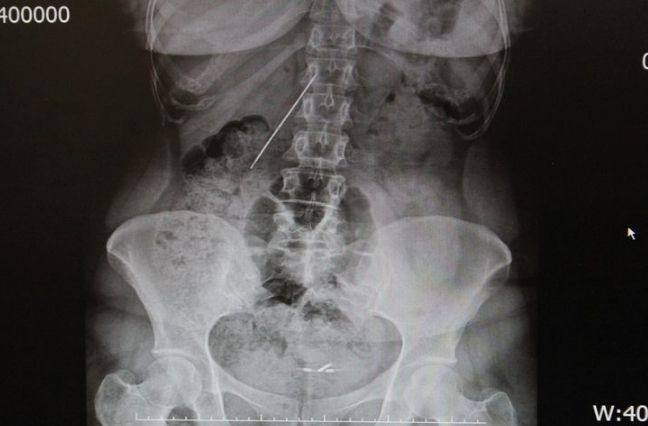

Konya'da doğduğu yıl vücuduna 15 cm uzunluğunda bir iğne batan Raziye Çalışkan'ın 26 yıllık kabusu son buldu.

Konya'da, doğduğu yıl vücuduna 15 santimetre uzunluğunda bir iğne batan Raziye Çalışkan, kahreden gerçeği 15 yaşına geldiğinde karın ağrısı ve ateşlenme şikayetiyle karşı karşıya kaldığında öğrendi. Doktorlar, zamanla hastanın yaşam kalitesini etkileyen iğnenin, sağ böbreğe yakın bir yerde ince ve kalın bağırsak arasında durduğu tespit etti. Ancak ameliyatla alınmak istenen iğne, vücutta yer değiştirince operasyon başarısızlıkla sonuçlandı.

Prof. Dr. Mehmet Arazi, başarılı bir operasyonla Çalışkan'ın vücudundan iğneyi çıkardı. Arazi, AA muhabirine yaptığı açıklamada, hastanın vücuduna batan iğnenin hayati bir bölgede olduğunu söyledi.

İşte Raziye Çalışkan'ın vücudundan çıkan iğne...